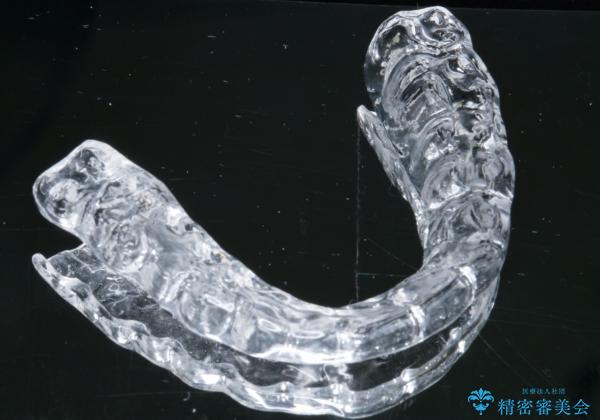

型取り(上下)をして自費のナイトガードを作製しました。

- 自費ナイトガード 3.3万円費用は治療当時の料金となります

保険のナイトガードと比べると割れにくくて、噛み合わせの歯と調整を行うために歯が変に負担がかかる事なく歯ぎしりや歯の破折を予防することができます。